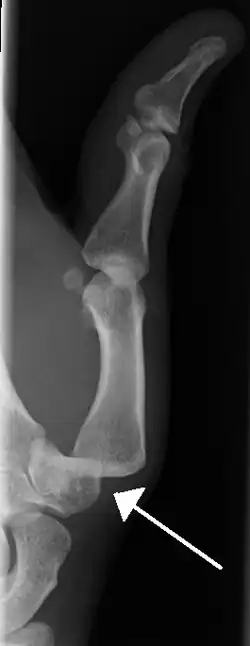

- Dislocation of the left index finger

- Radiograph of right fifth phalanx bone dislocation

- Radiograph of left index finger dislocation

- Dislocation of the carpo-metacarpal joint.

- Radiograph of right fifth phalanx dislocation resulting from bicycle accident

- Right fifth phalanx dislocation resulting from bicycle accident